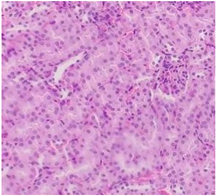

Finally, histopathological analysis of liver and kidney tissues from experimental subjects administered ME-Ip or DE-Ip revealed no evidence of tissue lesions, necrosis, inflammatory infiltrates, or structural alterations when compared to the control group (Table 10). These findings confirm the structural and functional integrity of these primary target organs commonly assessed in acute toxicity studies [104,105,106].

Histopathology of kidney and liver of mice treated at different doses of ME-Ip and DE-Ip during acute toxicity study.